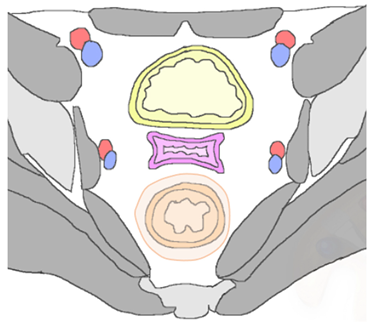

| Type of Recurrence | Imaging Findings |

|---|---|

| Regional | |

| Anterior Urinary bladder and urethra ![]() |

|

| Posterior Rectal or sigmoid colon ![]() | An infiltrating, spiculated mass, causing rectal or sigmoid luminal narrowing.

| Lateral Pelvic sidewall ![]() | Pelvic sidewall recurrence is defined as a tumor extending within 3 mm and abutting the obturator internus or piriformis muscles with concomitant loss of fat planes. Other findings include: